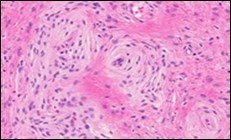

Figure 3.Soft tissue perineurioma with whorls and fascicles of neural cells displaying wavy nuclei, elongated cytoplasmic fibrils and intermingling of collagen fibres 13.

Soft tissue perineurioma with whorls and fascicles of neural cells displaying wavy nuclei, elongated cytoplasmic fibrils and intermingling of collagen fibres 13.